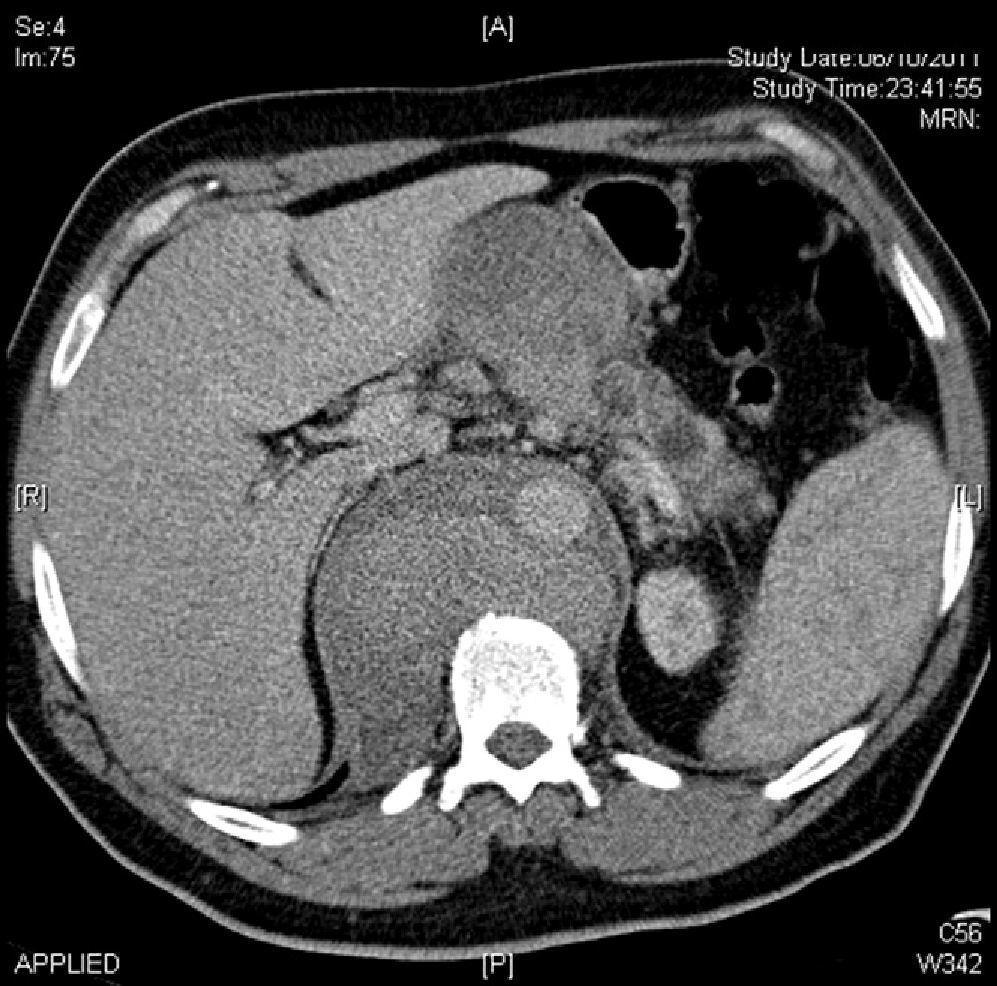

The patient was a 49-year-old male who was hospitalized for progressive abdominal pain accompanied by nausea, constipation and a weight loss of >15% over the course of the previous 2 months. Endoscopic study of the patient was normal. Abdominal CT scan identified an aortic pseudoaneurysm with a contained rupture 4cm from the origin of the superior mesenteric artery, adjacent to the first duodenal branch, measuring 9mm×8mm in diameter, and an aneurysm neck measuring 4mm (Fig. 1). We decided to implant an aortic prosthesis (31mm×15cm). The distal end was situated 1cm from the celiac trunk and was sealed with a tri-lobe balloon catheter (Fig. 2).